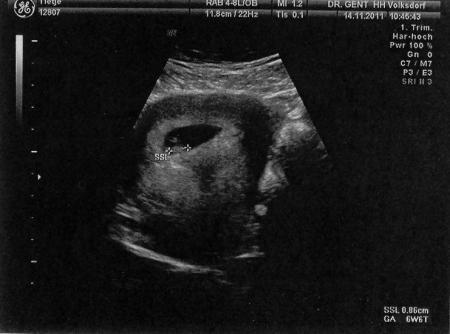

ach so. nochmal zum vergleich ein us bild von 6+6. über den bauch geschallt. denke nicht das es anders oder schlechter ist als die bilder beim vaginalen us.

Bild zu